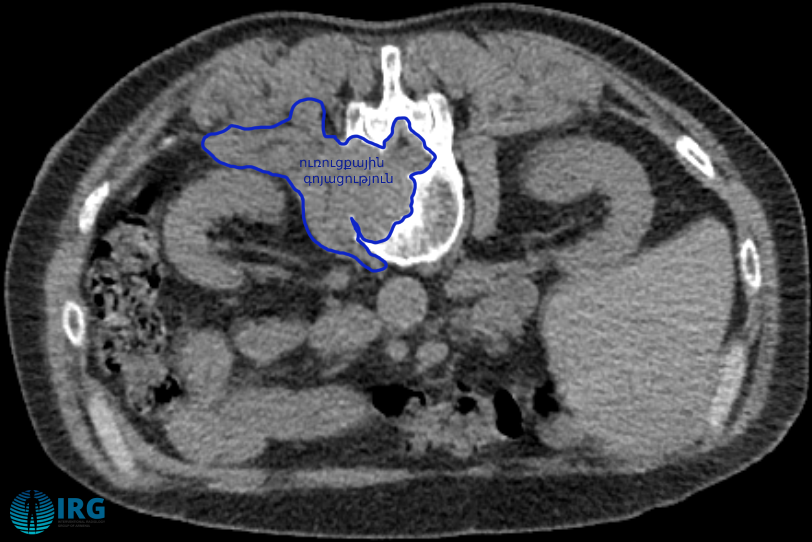

ՀՇ պատկերները միջամտության ընթացքում